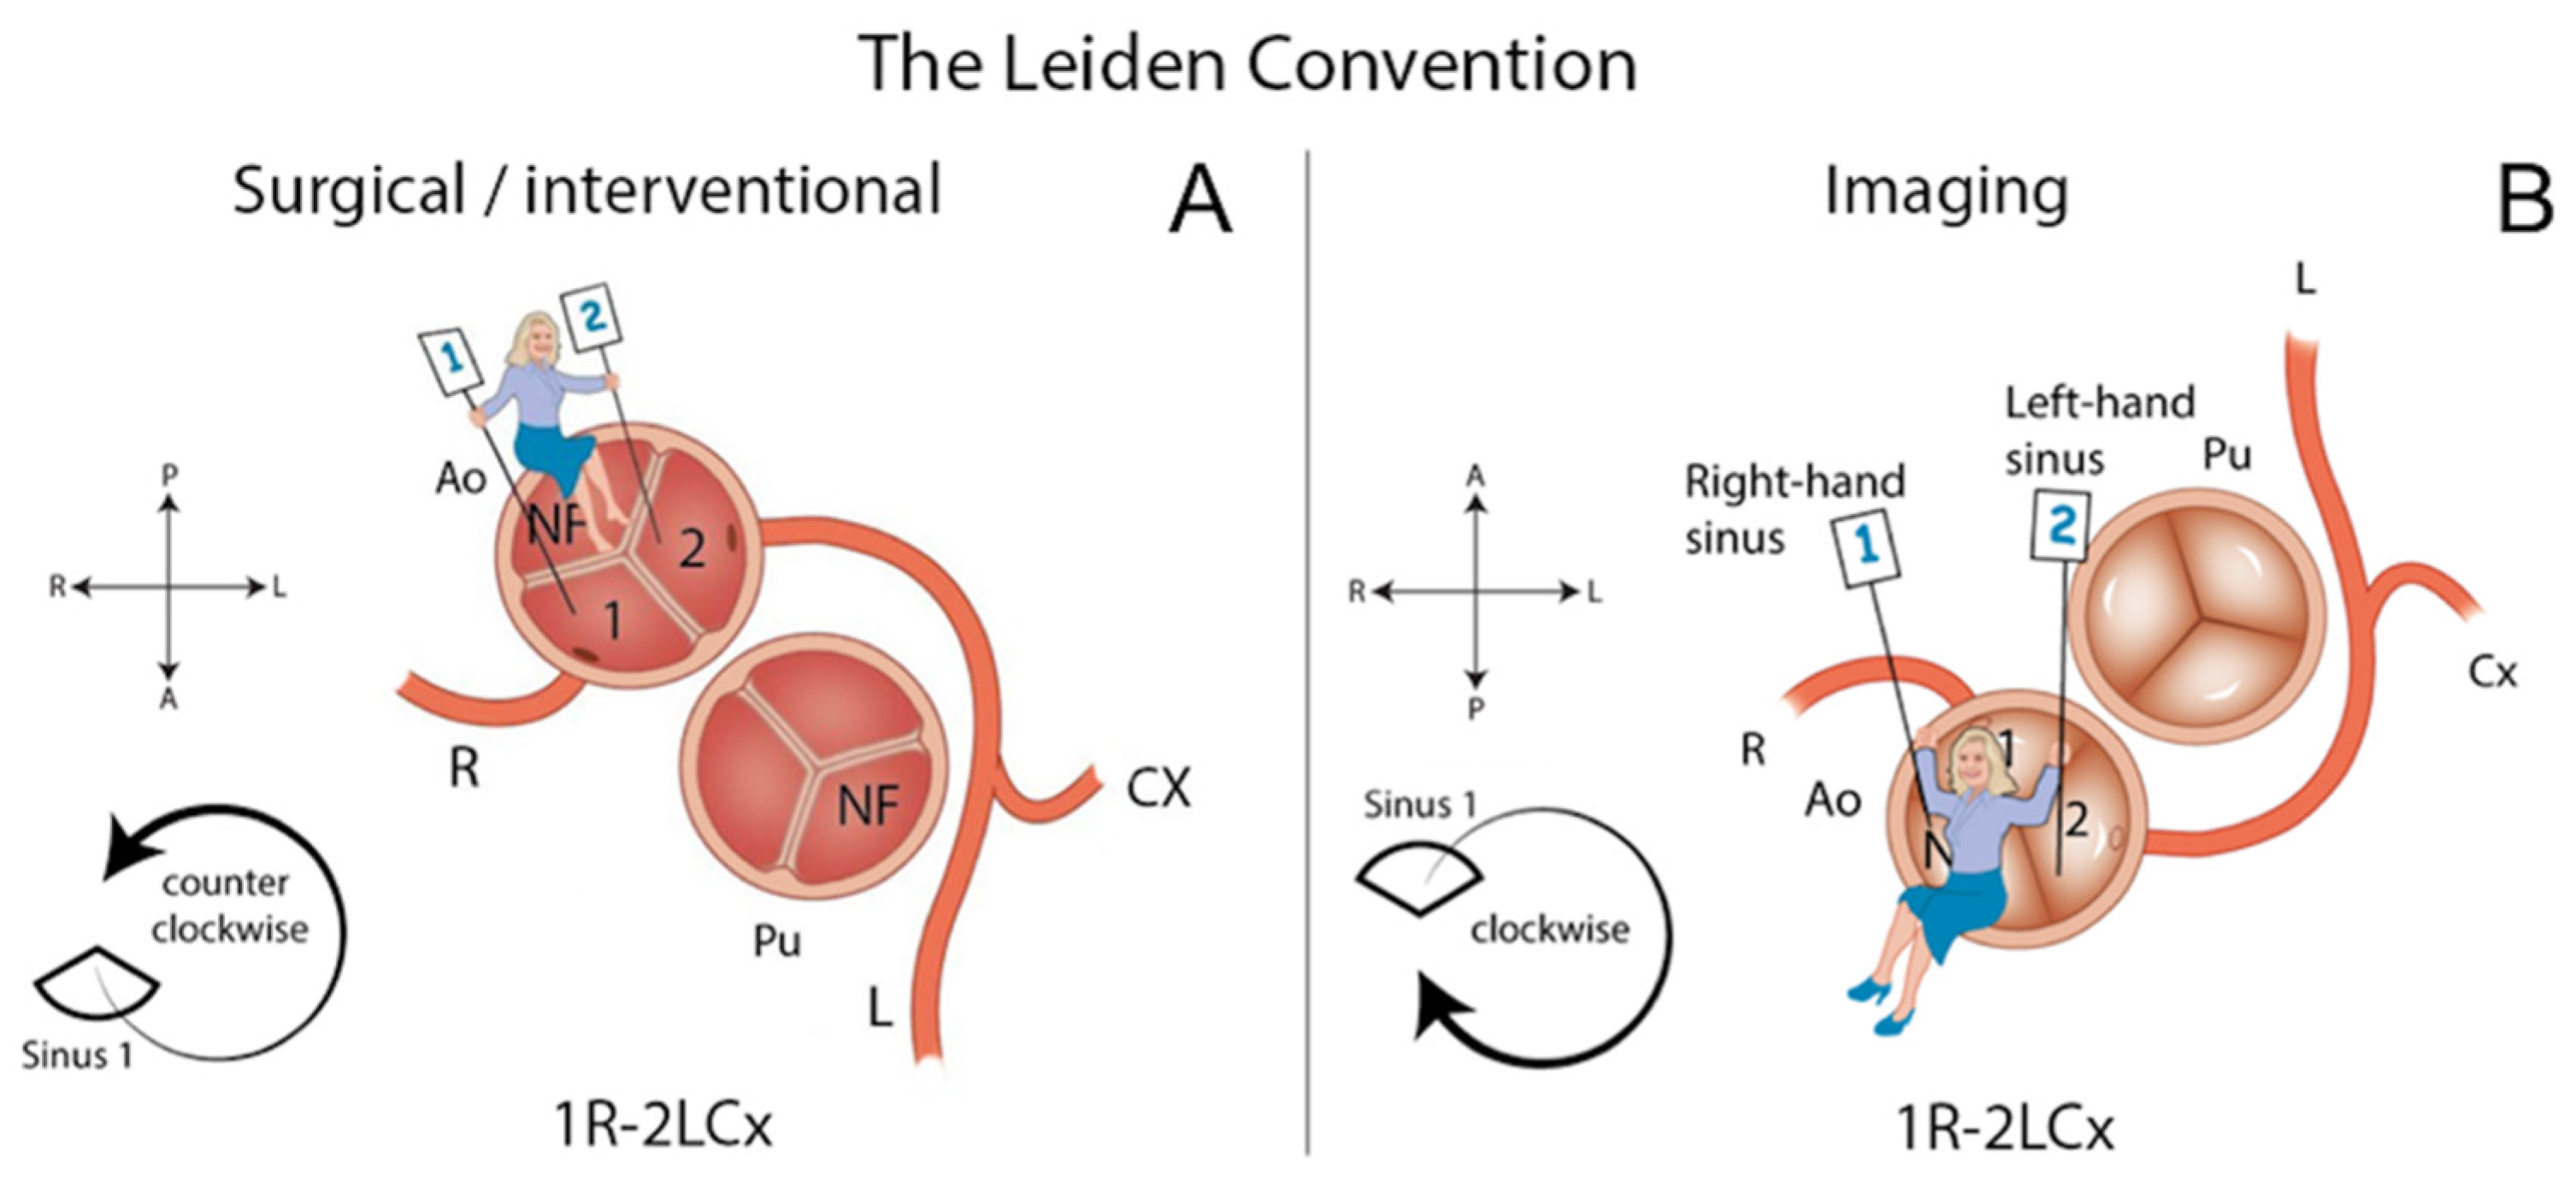

3.2. Leiden Convention Coronary Coding System